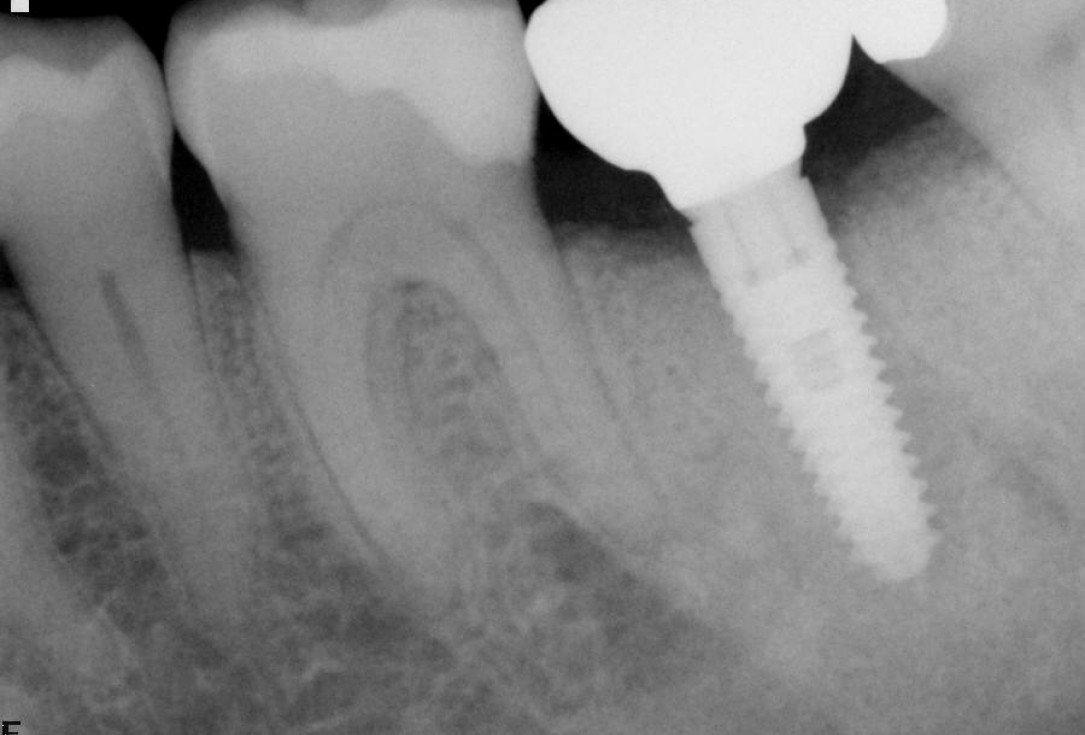

botiss cerabone® & Jason® membrane for GBR - Clinical case by Dr. S. Kovalevsky

Implant insertion in atrophic alveolar ridge